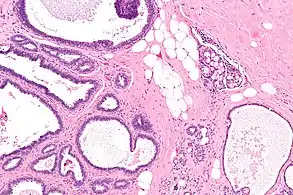

Collagenous spherulosis is characterized by a tubular/cribriform architecture with intratubular eosinophilic material that classically is arranged like the spokes of a wheel ("radial spikes"). There is usually no mitotic activity, and two cells populations (epithelial & myoepithelial) are present, like in benign breast glands.

The lesions are typically small (less than 50 spherules per lesion, less than 100 micrometers in size) and may be multifocal.